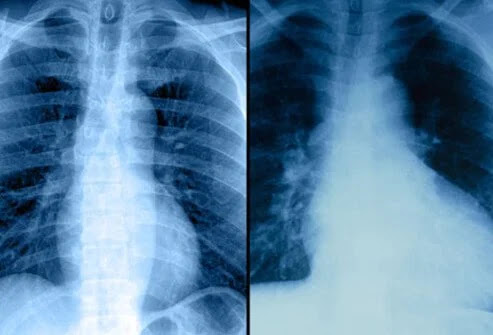

Έλεγχος καρδιακών παθήσεων: Ακτινογραφία θώρακα

Μια ακτινογραφία θώρακος μπορεί να βοηθήσει στον προσδιορισμό εάν κάποιος έχει διογκωμένη καρδιά ή συσσώρευση υγρού στους πνεύμονες λόγω καρδιακής ανεπάρκειας.

Οι ακτινογραφίες θώρακα μπορούν να παρέχουν περιορισμένες πληροφορίες σχετικά με την κατάσταση της καρδιάς. Οι ακτινογραφίες θώρακα χρησιμοποιούνται για να παρέχουν στον γιατρό μια εικόνα τόσο της καρδιάς όσο και των πνευμόνων για να καθοριστεί εάν υπάρχουν ανωμαλίες. Αυτές οι δύο ακτινογραφίες δείχνουν μια σχετικά φυσιολογική καρδιά στα αριστερά. Στη δεξιά ακτινογραφία, μια διογκωμένη καρδιά (κυρίως η αριστερή κοιλία) φαίνεται εύκολα και υποδηλώνει ότι ο κύριος θάλαμος άντλησης της καρδιάς δεν λειτουργεί κανονικά. Επιπλέον, οι ακτίνες Χ μπορεί να δείχνουν συσσώρευση υγρού στους πνεύμονες, πιθανώς από καρδιακή ανεπάρκεια.